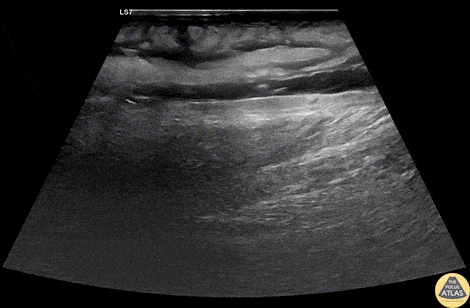

A 60s M with multiple medical co-morbidities including type 2 diabetes mellitus with multiple prior toe amputations, CHF, COPD and chronic alcohol abuse presented with rapidly worsening leg pain after minor trauma the day prior to presentation. He was in significant pain and had a warm, red, and edematous lower extremity with a focal wound overlying the anterior lower leg. He was febrile and tachycardic, but normotensive. He was resuscitated and given broad spectrum antibiotics and rapid surgical consultation was obtained. POCUS of the affected area was performed and is shown here. In these longitudinal views of the affected area, cobblestoning is seen superficially, indicating cellulitis. Fluid is also seen tracking more deeply along the fascial planes, just superficial to the muscle. This patient was taken emergently to the OR where debridement confirmed necrotizing fasciitis without involvement of the underlying muscles. The patient was kept in the surgical ICU for further resuscitation, his blood cultures and tissue culture became positive for Group A Strep pyogenes, and he underwent multiple subsequent debridements for further management. Dr. Phil Breslow, PGY2 and Dr. Anna Engeln Denver Health Residency in Emergency Medicine